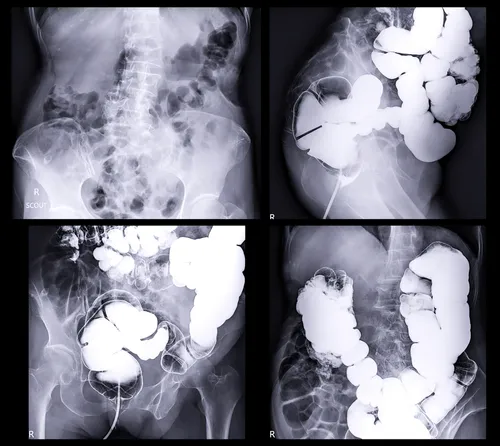

La prueba más efectiva sigue siendo la colonoscopía.“Es un estudio que se hace bajo anestesia. El doctor pone un tubo con una cámara pequeña y mira todo el intestino. Lo bueno es que también puede quitar pólipos y hacer biopsias”, explica.